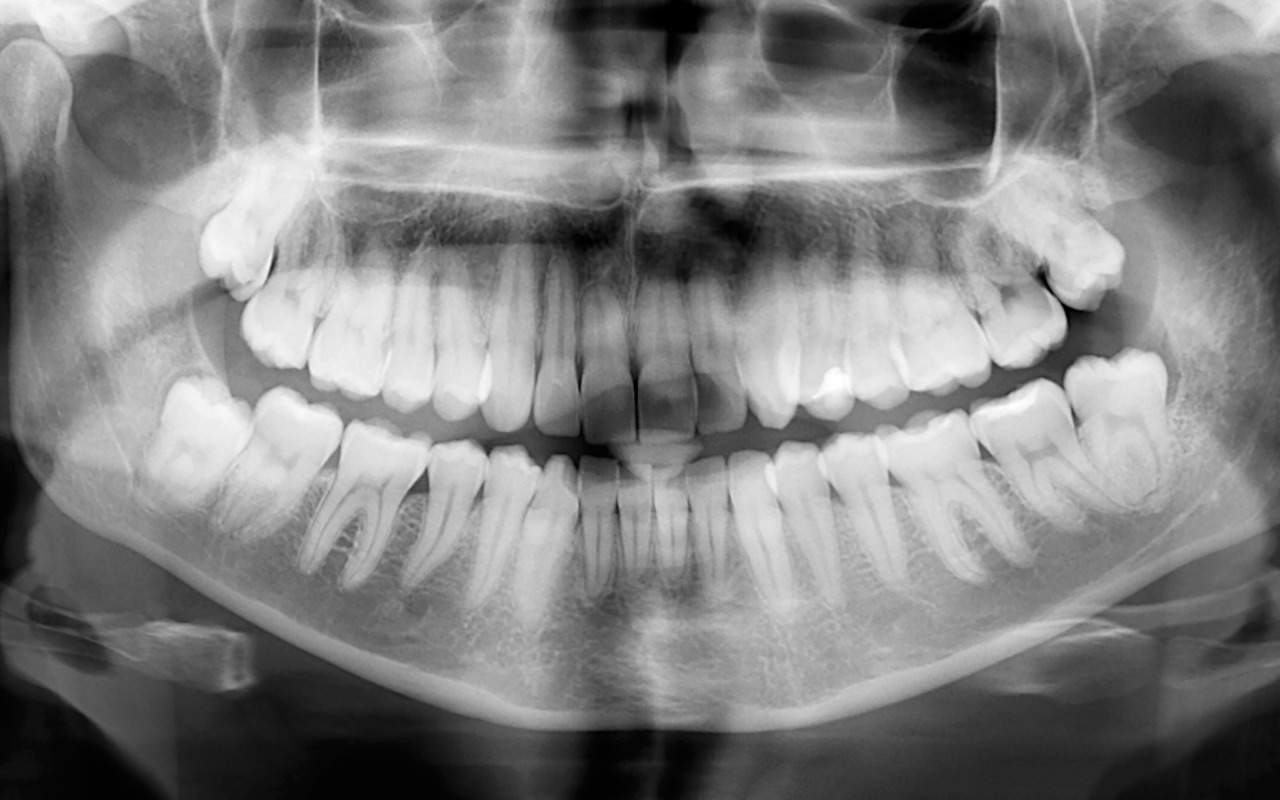

![]() | Digitales RöntgenDigitales Röntgen: Strahlungsarm und präzise |